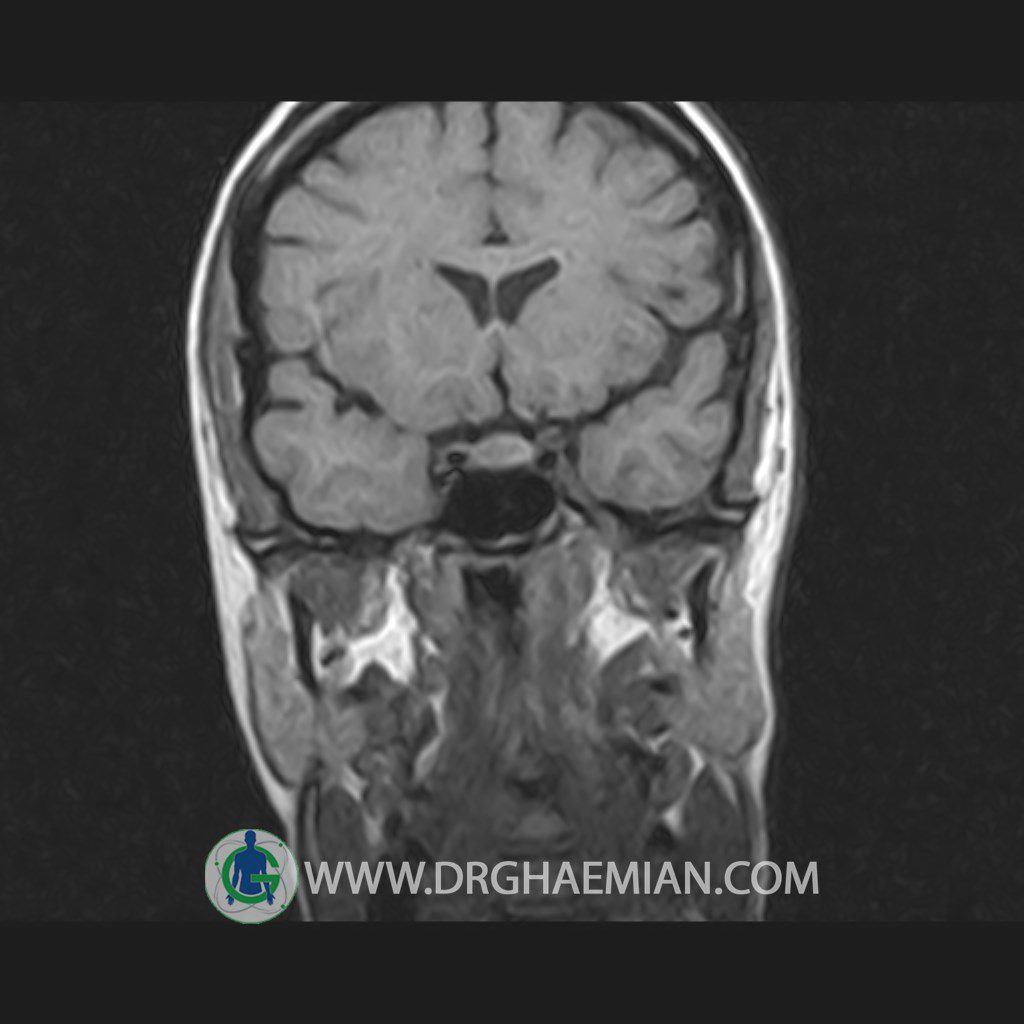

پزشکان اغلب از تصویربرداری ام آر آی برای تشخیص و درمان عارضه های پزشکی که فقط با استفاده از اشعه ایکس یا میدان مغناطیسی و امواج رادیویی قابل مشاهده است، استفاده می کنند. دستگاه ام آر آی تصاویر دقیق از ساختار های داخلی بدن ایجاد می کند. در این کیس هیپرپلازی هیپوفیز و آدنوم مشاهده می شود.

HYPOPHYSIS MRI

(with and without contrast)

Technique: Axial , coronal T1 , Axial , coronal , sagittal T2 , Axial, coronal T1 post Gd & 64 dynamic thin coronal slices.

The sella shows normal size , position and configuration .

The borders of its floor and walls are smooth and sharply defined .

The infundibulum is centered and of normal size .

The optic chiasm and suprasellar spaces appear normal .

The cavernous sinus and imaged portions of the internal carotid artery and carotid siphon are unremarkable .

Evaluable portions of the neurocranium show no abnormalities .

The sphenoid sinus is clear and pneumatized .

– Mild convexity at superior border of pituitary gland with post contrast homogeneous enhancement suggestive for pituitary hyperplasia & iso signal adenoma

is seen